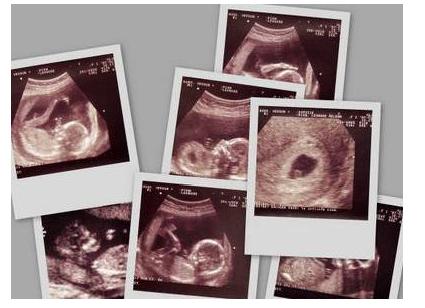

是不是准妈妈们从怀孕初期就开始期待孕子里的孩子是男是女了?因为国家

并不提倡鉴定胎儿性别,所以宝妈们对肚子里的宝宝究竟是男是女有着很大

的好奇心。在这里小编就教大家一个利用B超单上的数据来看男女的方法,

来一解准妈妈们的好奇心。